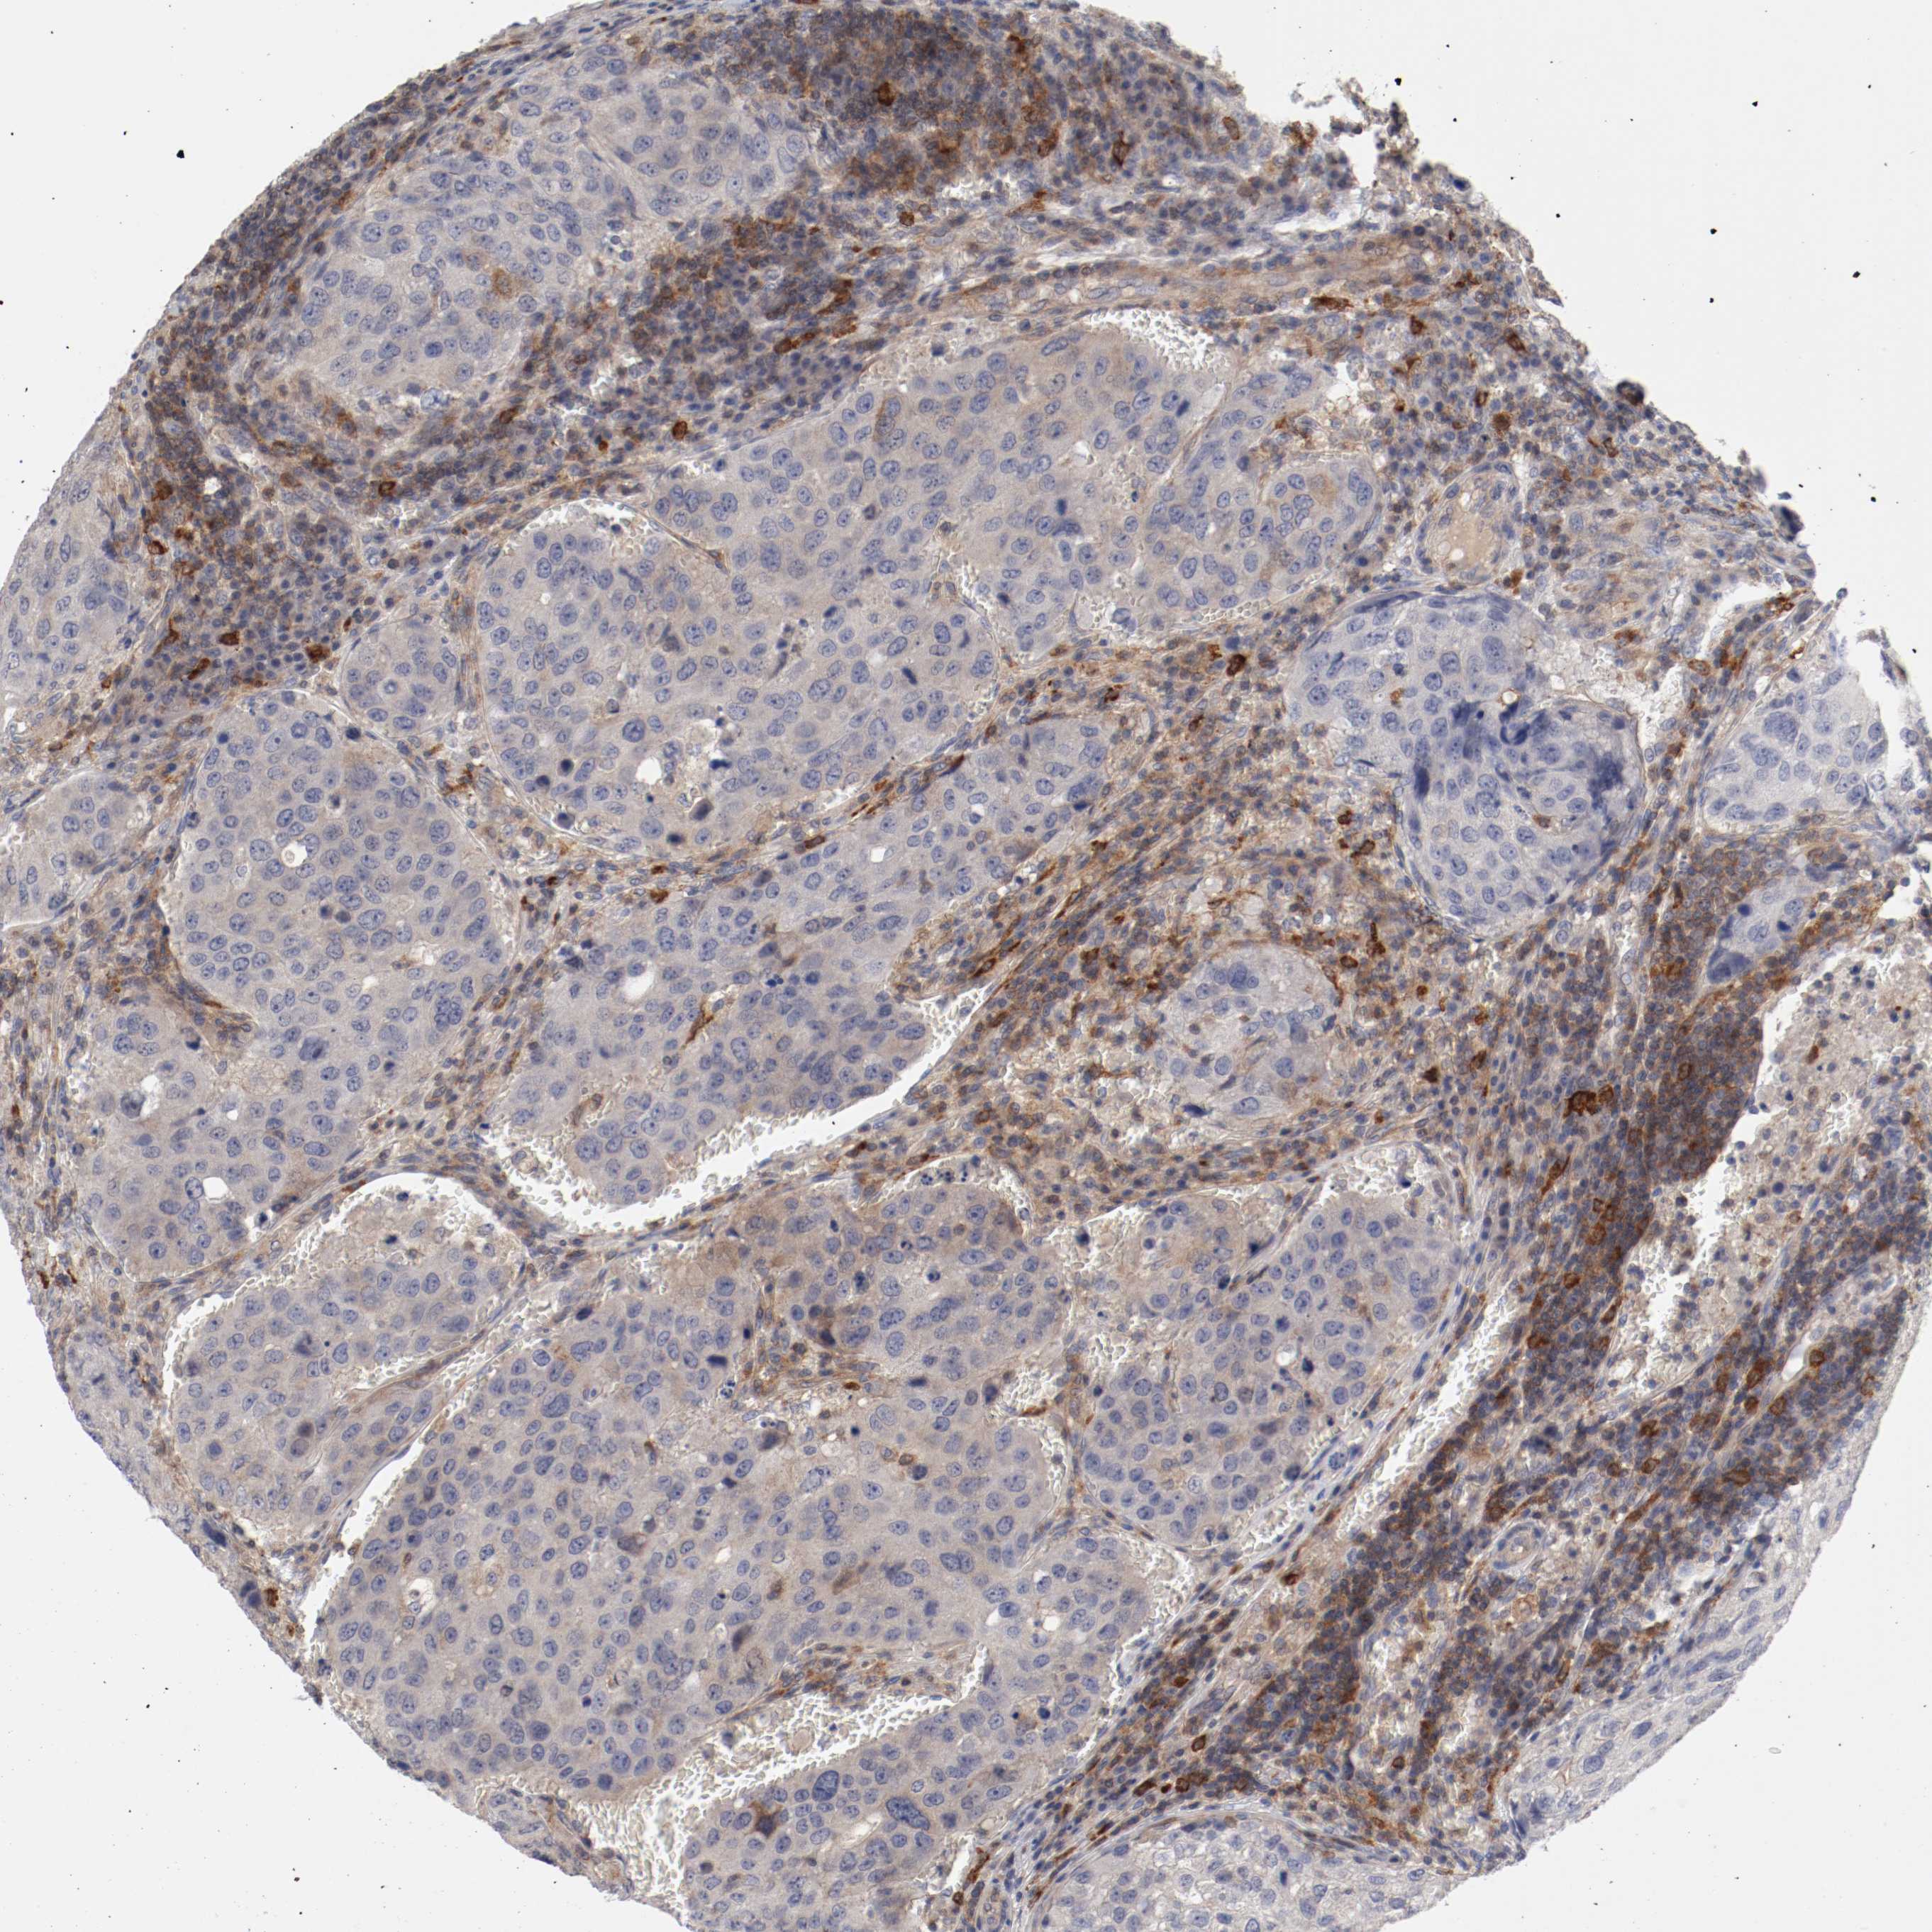

UROTHELIAL CANCER - Protein expressioni

A mouse-over function shows sample information and annotation data. Click on an image to view it in a full screen mode. Samples can be filtered based on level of antibody staining by selecting one or several of the following categories: high, medium, low and not detected. The assay and annotation is described here.

Antibody stainingi

Antibody staining in the annotated cell types in the current human tissue is reported as not detected, low, medium, or high, based on conventional immunohistochemistry profiling in selected tissues. This score is based on the combination of the staining intensity and fraction of stained cells.

Each image is clickable and will lead to virtual microscopy that enables deeper exploration of all samples and also displays staining intensity scores, fraction scores and subcellular localization as well as patient and tissue information for each sample.

Antibody HPA027956

Antibody CAB004350

Staining

High

Medium

Low

Not detected

Intensity

Strong

Moderate

Weak

Negative

Quantity

>75%

75%-25%

<25%

None

Location

Nuclear

Cytoplasmic/membranous

Cytoplasmic/membranous,nuclear

Urothelial carcinoma, Low grade

Urothelial carcinoma, High grade